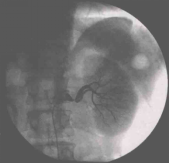

肾动脉造影检查显示左肾动脉起始部存在90%狭窄,呈偏心性,位于肾动脉分为前后两支的分叉处(图1);因此难以行肾动脉支架植入术。经泌尿外科会诊后转科行自体肾移植。术后第3天开始停用所有降压药物,血压波动于115~125/70~80 mmHg。术后肾动脉病理示“动脉粥样硬化”。目前随访至术后3年,应用一种钙离子拮抗剂血压控制良好;24小时尿蛋白定量0.35 g;SCr 123μmol/L。

图1. 肾动脉造影